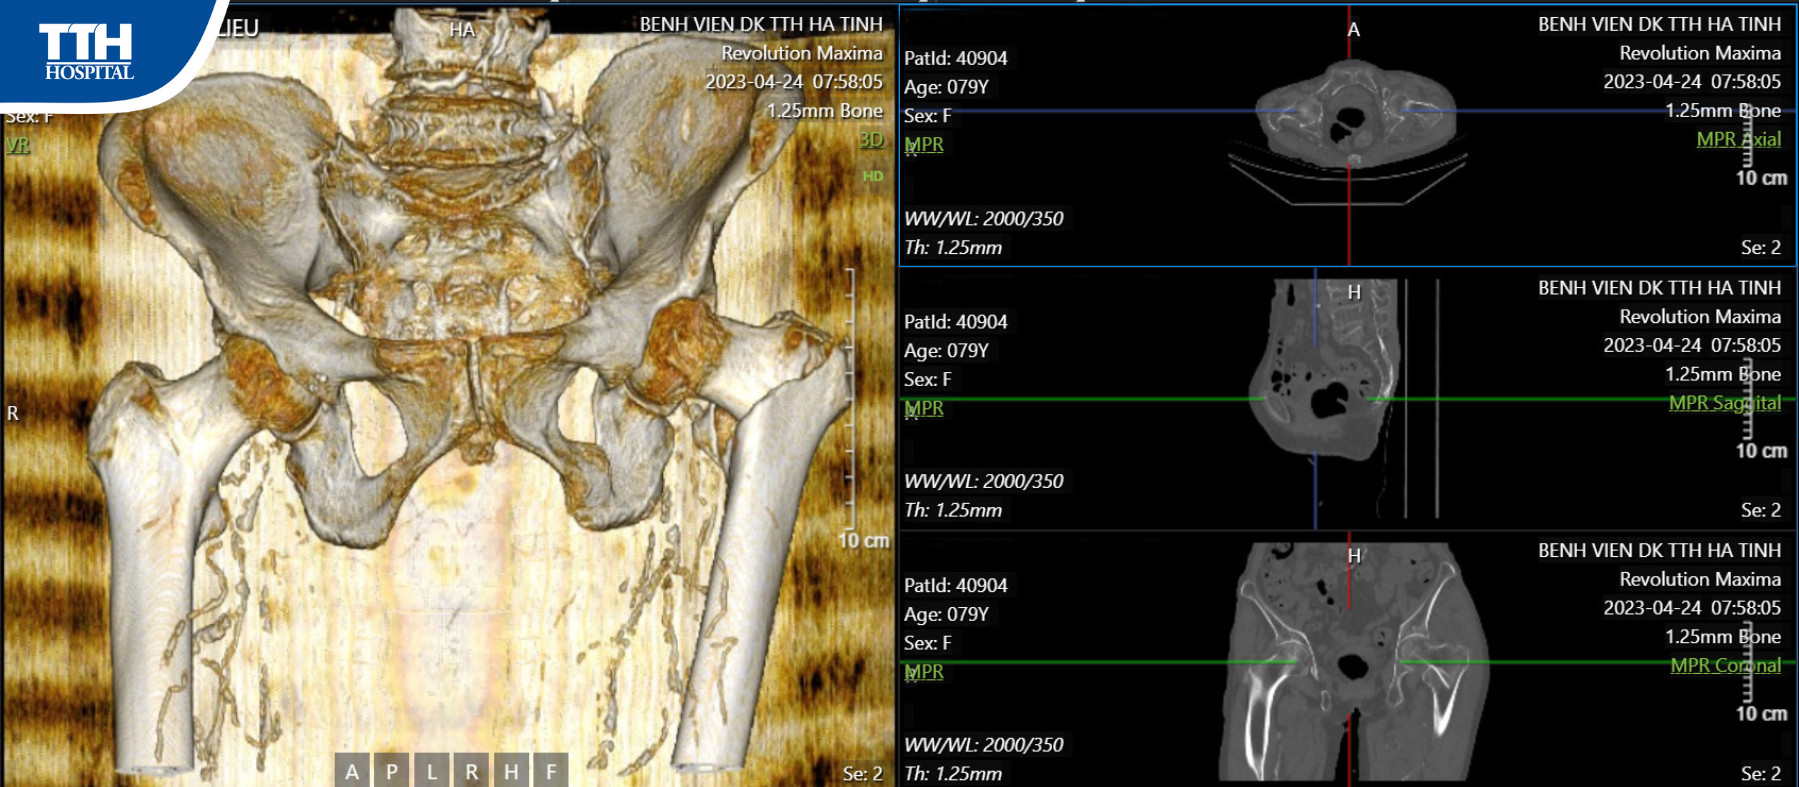

Sau khi thăm khám và làm các xét nghiệm cận lâm sàng, kết quả chụp MRI cho thấy bệnh nhân bị gãy liên mấu chuyển xương đùi trái cần phẫu thuật thay khớp háng nhân tạo.